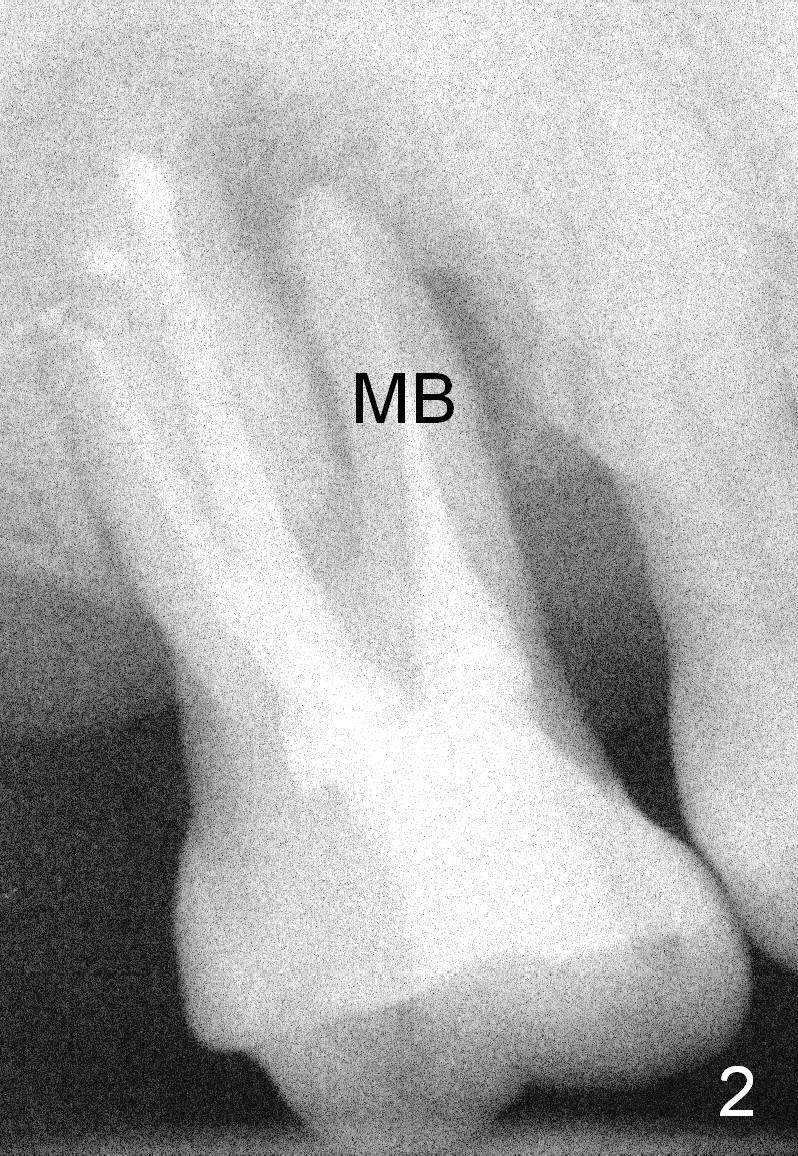

Two years post RCT, there is radiolucency around the MB root of the tooth #3 (Fig.1,2). Eleven days later, there is acute infection associated with MB and DB root fracture (Fig.3). According to the X-ray taken 11 days earlier (Fig.1,4), a long tissue-level implant (6x17 mm) is suitable for the site. In accordance with CBCT (coronal (Fig.5) and sagittal (Fig.6) sections) taken prior to RCT, a short bone-level implant (6.9x10 mm) is a more reasonable choice.

After extraction, the socket will be studied to determine where the bone is and where bony defects are for the site of the initial osteotomy. Start with 2 mm pilot drill or RT2, apparently ~ 6 mm depth, followed by reamers 2.5-3.5 mm and Tatum taps 4.5-7x17 mm (14 mm depth from gingival margin). Use a latch adapt with the torque wrench. Due to severe bone loss, the tap should not be too large (6 mm). If insertion torque is high and bone morphology is favorable, change to DIO taps and take necessary PAs to decide the length of the implant relative to the sinus floor and trajectory. If the depth is 10 mm or less, use SM; 12 mm UF. Based upon the most recent X-ray (Fig.3 with large lesion), the implant should be large and long (Fig.7: 7x17 mm).